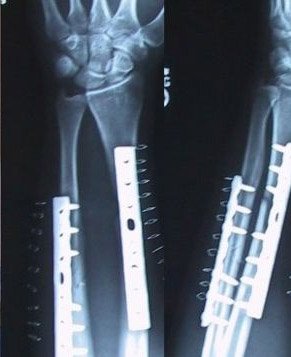

Der Unfall - ist meist schneller passiert als man denkt...